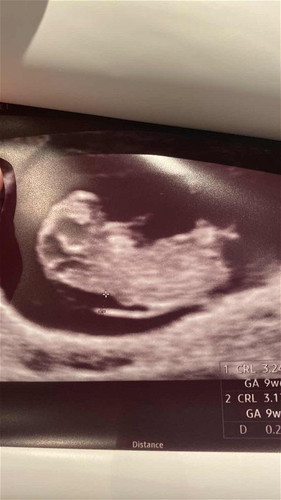

9wk6d ultrasound shows relatively high NT

Went for my 2nd routine check & gynae spotted this “gap” at the back that measures 2.8mm. My husband & I decided to make an appointment for both Oscar & NIPT as soon as we are able to. Still, I just can’t help but worry over it. Anyone who can share past experiences to ease my concern would be highly appreciated 🙏🏻 Update 23/7/23: FTS & NIPT both came out low risk 🥹 #firsttimemom #firstbaby